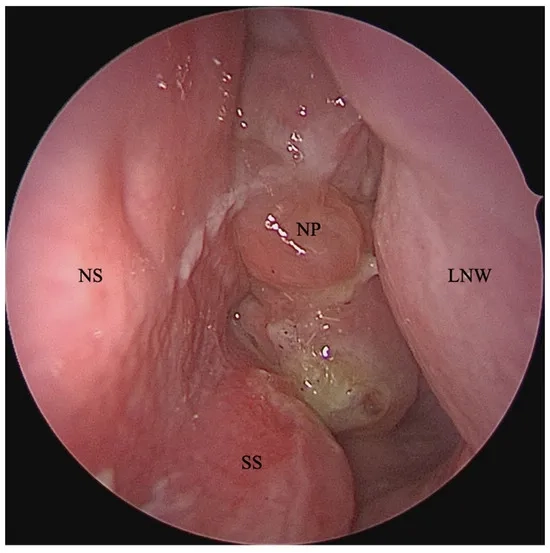

• Nasal polyps, which are soft, noncancerous growths on the lining of the sinuses, can block nasal passages and lead to chronic inflammation.

Endoscopic image showing nasal polyps